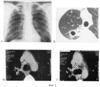

Сущность предлагаемого изобретения представлена на фиг.1, 2 и 3. На фиг.1 – данные рентгенологического обследования больного (пример 1), на фиг.2 и 3 – данные рентгенологического обследования больного (пример 2).

При рентгенологическом обследовании от 29.03.07 (Фиг.1-А, Б) отмечается сохранение полости распада (каверны) со сформированной стенкой в S2 правого легкого размером 2,4×3,6 см, на фоне фиброзно-перестроенного легочного рисунка и разнокалиберных очагов. Дополнительно визуализируются (Фиг.1-В, Г) увеличенные до 1,3 см в наибольшем размере лимфоузлы правой трахеобронхиальной и бронхопульмональной группы. Структура лимфоузлов неоднородна за счет участков повышенной плотности в центральных отделах лимфоузла. Неоднородность структуры позволяет сделать вывод о туберкулезном лимфадените.